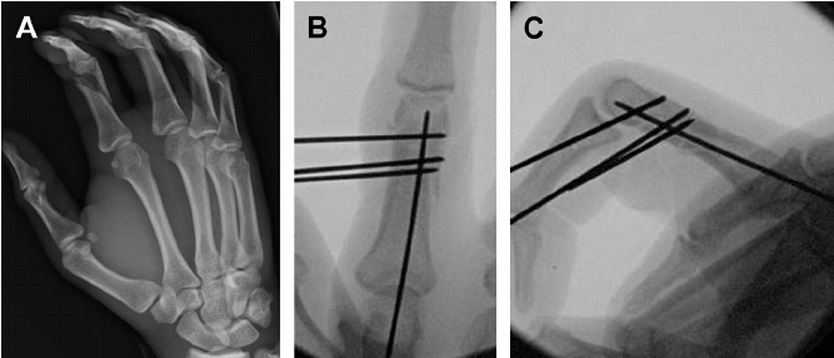

4-2: تشخیص و درمان شکستگی اسکافوئید: معاینه و تصویر برداری رادیوگرافیک اقدام اول است. در مواردی که شکستگی همراه با جابجایی باشد درمان آن بصورت جااندازی و استفاده از پیچ برای بیحرکت کردن قطعات شکسته شده است.

در این موارد جااندازی شکستگی ممکن است بصورت بسته یا باز باشد. گاهی اوقات حتی با وجود شکسته بودن استخوان، این شکستگی در رادیوگرافی قابل مشاهده نیست. بنابراین در مواردی که پزشک معالج مشکوک به این شکستگی بوده ولی در رادیوگرافی نکته غیر طبیعی دیده نمی شود، دست بیمار از کف دست تا آرنج (گچ اسپایکای شست) گچ گرفته می شود و پس از دو هفته گچ خارج شده و مجددا از ناحیه مچ دست عکس برداری می شود. اگر شکستگی واقعا وجود داشته، ولی در رادیوگرافی اولیه دیده نشود، در رادیوگرافی که بعد از دو هفته تهیه میشود قابل مشاهده است.راه دیگر این است که در همان روز معاینه اولیه که رادیوگرافی ساده شکستگی را نشان نداده است از بیمار ام آر آی و یا اسکن رادیوایزوتوپ به عمل آید. این دو روش تصویربرداری می توانند با حساسیت بیشتری شکستگی را کشف کرده و نشان دهند .